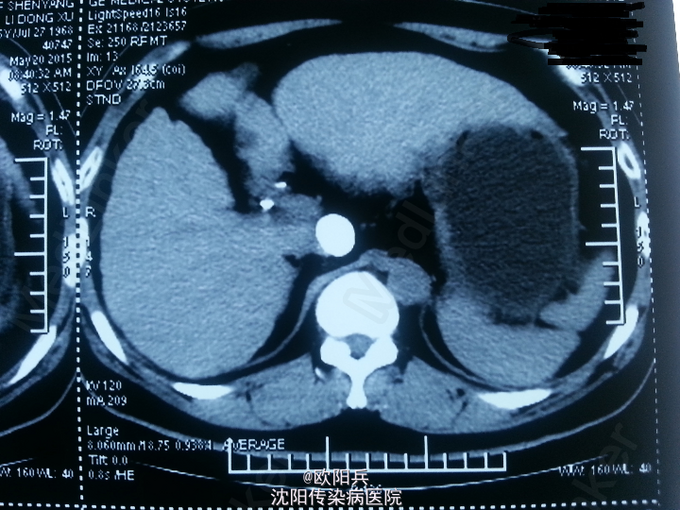

查体:神清语明,面色晦暗,巩膜无黄染,浅表淋巴结无肿大,心肺听诊无异常,腹软,无压痛,肝脾肋下未触及,移动性浊音阴性,肠鸣音正常,双下肢无水肿,扑翼样震颤阴性。 化验:血细胞分析(五分类):*白细胞计数 3.6 10^9/L、*血小板计数 113.0 10^9/L↓、*血红蛋白 166 g/L、中性粒细胞百分比 60.7 %,肝功酶谱:*丙氨酸氨基转移酶 92 U/L↑、*总蛋白 75.0 g/L、*白蛋白 47.0 g/L、*总胆红素 24.0 umol/L↑,糖化血红蛋白检测:糖化血红蛋白 13.50 %↑,*葡萄糖测定:*葡萄糖 15.66 mmol/L↑,血清离子测定:*钾 4.61 mmol/L,肾功能检测:*尿素 5.25 mmol/L、*肌酐 47.3 umol/L↓,血浆氨测定:血氨 29.00 ,凝血五项:凝血酶原时间 9.5 秒↓,乙肝六项:乙型肝炎病毒表面抗原 阳性(+) ↑、乙型肝炎病毒e抗体 阳性(+) ↑、乙型肝炎病毒核心抗体 阳性(+) ↑,丙型肝炎抗体测定(发光法):丙肝抗体 0.01 S/CO,甲胎蛋白测定:甲胎蛋白 7.29 ng/mL。 心电图:正常。 彩超(2015-5-17我院门诊):肝硬化、脾面积大,肝右叶高回声性质待定。 CT:1、肝尾叶占位介入术后改变;2、脾大,肝硬化,肝内多发RN可能性大。

根据患者病史、临床表现及目前辅助检查分析诊断:1、乙肝肝硬化 代偿期 活动性(C-P A级);2、原发性肝癌(肝尾叶)介入术后;3、2型糖尿病。主要诊断依据有: 1、患者乙肝肝硬化、肝癌介入病史明确,2型糖尿病史2年余。2、查体:面色晦暗,移动性浊音(-)。3、化验:患者肝功示转氨酶升高,无低白蛋白血症,C-P评分5分,支持乙肝肝硬化 代偿期 活动性(C-P A级)。糖化血红蛋白 13.50 %↑,葡萄糖 15.66 mmol/L↑,支持2型糖尿病。关于鉴别诊断,患者无酗酒史,不考虑酒精性肝病。其肝癌经DSA下肝动脉造影证实,无需鉴别。患者复查增强CT示肝尾页栓塞密实,边缘无强化,可暂无进一步处理,定期复查。本次住院行常规护肝抗肿瘤治疗。

患者半年前行介入治疗,效果如图,此类患者需密切观察肿瘤进展,目前暂无特殊处理。